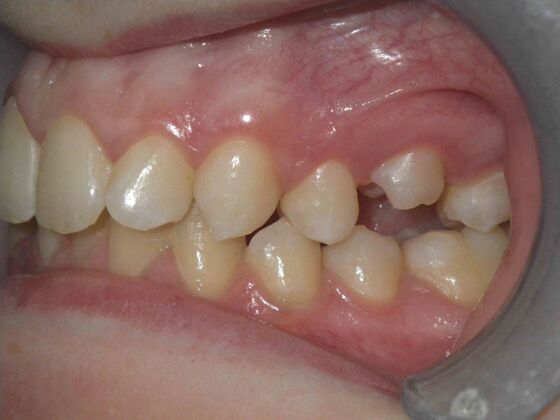

Orthodontics: Case 4

Description

Patient presents with constricted upper and lower arches, numerous crossbites on right side, with upright central incisors on upper arch that will need to be flaired to provide adequate lip support. I decided to use on this case self ligating brackets, to help with expansion purposes. This case turned out very well with flairing of upper centrals, crossbite corrections, expansion of arches, as well as establishing better arch form and symmetry.